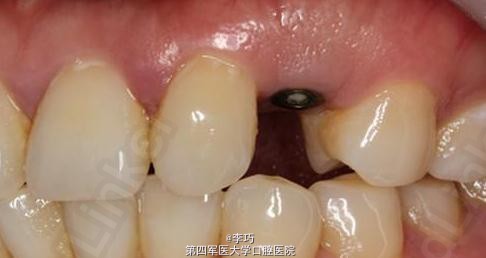

效果很好,患者满意